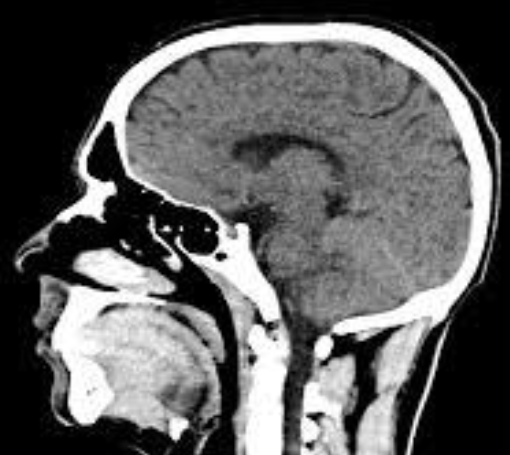

A CT scan of a person's head.

You will have your pictures taken in a room using a CT scanner. It is a very special scanner that uses x-rays to produce very detailed images of your brain.